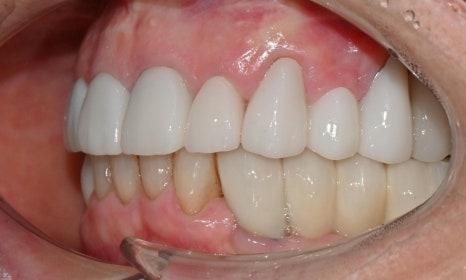

2026.2 치료 마무리 후 사진 - 연세정원치과

이와 같이 임시치아 단계에서 충분히 디자인을 조정하고 상담을 마무리하면, 기공소에 보다 정확한 디자인을 전달할 수 있어 최종 보철 만족도가 크게 높아집니다. 웃을 때나 말할 때 앞니 보철이 보이고, 아래 앞니도 추후 보철 예정이시라서 보철 색상은 다른 보철에 맞추기보다, 환자가 원하는 정도로 밝게 제작하였습니다.

치료 마무리 후 smile 사진 - 연세정원치과

앞니 보철 치료는 단순히 크라운을 새로 만드는 치료가 아니라, 잇몸 상태, 치아의 마모와 위치, 스마일라인, 발음과 식사까지 함께 고려해야 하는 종합적인 치료입니다. 특히 오래된 보철을 교체하는 경우에는 보이지 않던 문제들이 함께 발견되는 경우가 많아, 단계별 계획과 임시보철을 통한 검증 과정이 최종 치료 결과의 정확성과 안정성을 결정짓는 중요한 요소가 됩니다. 이러한 접근을 통해, 심미성과 기능을 동시에 만족시키는 치료 결과를 얻을 수 있으며, 장기적인 유지와 환자 만족도 또한 크게 향상됩니다.

이번 케이스는 임시치아 단계에서 환자분과 충분히 소통하며 디자인을 조정한 덕분에, 기능과 심미를 모두 만족시키는 방향으로 치료를 진행할 수 있었습니다. 특히 앞니는 웃을 때나 말할 때 거의 항상 보이는 부위이기 때문에, 조금만 모양이나 색이 어긋나도 인상이 크게 달라질 수 있으므로, 얼굴과 미소 전체와 조화를 이루는 보철을 만들기 위해 환자분과 충분한 소통을 통해 세밀한 디자인 조정과 단계별 검증을 시행할 수 있었습니다.